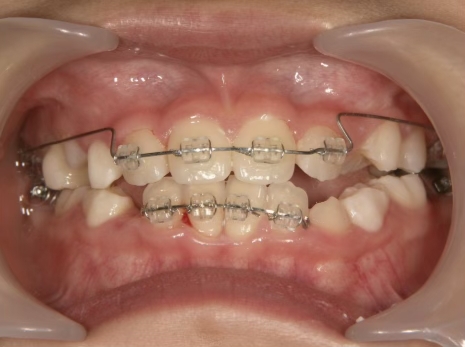

治療中➁ 小3:9y1m

前歯をブラケットで並べる